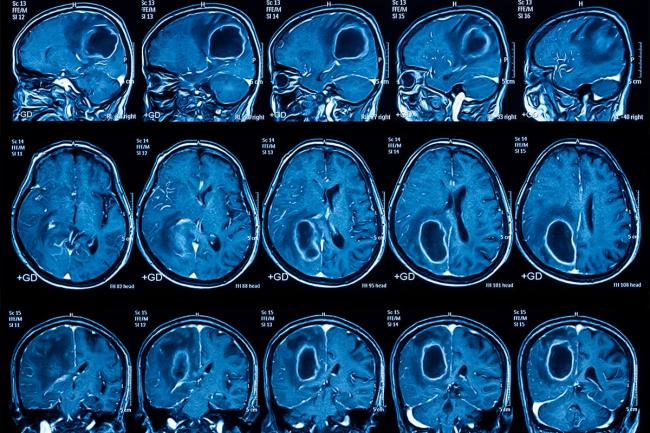

Il glioblastoma è uno dei tumori cerebrali maligni più aggressivi e a più rapida crescita. Sebbene raro, è il tumore cerebrale maligno primario più comune negli adulti, colpendo circa tre persone su 100.000. È resistente al trattamento e spesso recidiva. Gli scienziati lo hanno definito un "tumore freddo" per la sua capacità di nascondersi al sistema immunitario. Sebbene gli scienziati possano in qualche modo smascherare questo travestimento, i farmaci attuali si degradano rapidamente e possono essere somministrati direttamente al cervello attraverso iniezioni rischiose. I ricercatori del Siteman Cancer Center dell'Università di Washington hanno adottato un approccio diverso, sviluppando un metodo non invasivo che attiva la risposta immunitaria per attaccare il glioblastoma. In collaborazione con i chimici della Northwestern University, hanno creato speciali strutture di dimensioni nanometriche (nanoparticelle) sotto forma di acidi nucleici sferici (SNA) a base d'oro. L'idea era di somministrarle all'organismo attraverso il naso, sotto forma di gocce nasali. Le nanoparticelle viaggiano attraverso la mucosa nasale, seguendo le vie nervose, fino al cervello e, al suo interno, all'ambiente tumorale. Una volta che le nanoparticelle raggiungono il tumore o almeno si avvicinano ad esso, attivano i macrofagi, le cellule immunitarie che solitamente proteggono il glioblastoma, in modalità antitumorale. Si innesca una reazione immunitaria: viene attivata una via immunitaria intrinseca (la via STING), che è una delle vie di risposta immunitaria dell'organismo a virus e tumori.